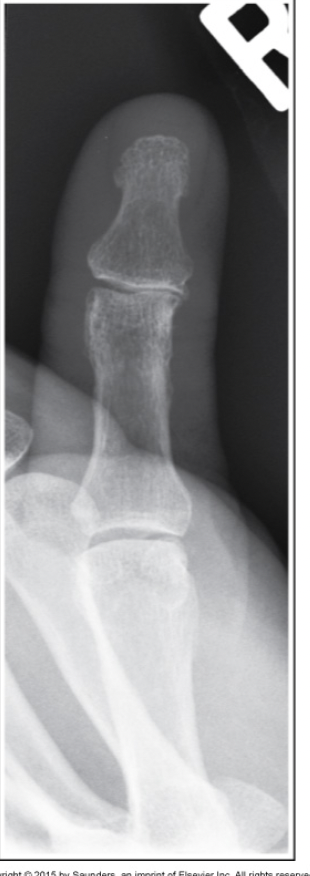

What image criterion is not met on this AP projection of the thumb?

a.Interphalangeal joint space in profile

b.Proximal and distal phalanges demonstrated

c.First metacarpal-phalangeal joint is free of superimposition

d.First metacarpal-carpal joint is shown free of superimposition

A